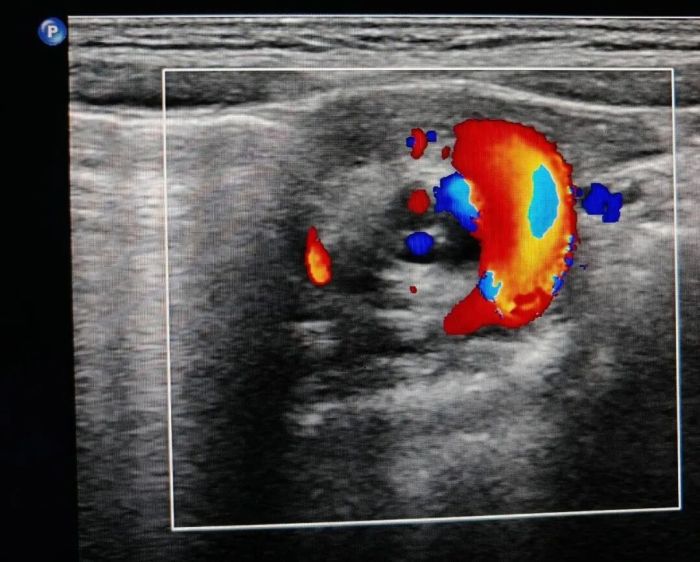

超声医学科接到申请后,立即启动儿童急腹症应急检查流程。检查中,囡囡因不适哭闹剧烈、配合度差,小儿超声组王建香医师一边耐心安抚,一边规范、细致、全面地完成腹腔超声及胃肠道超声联合检查,同时仔细询问病史,得知囡囡既往长期存在消化不良症状。凭借丰富的临床经验与敏锐的专业判断力,她迅速识别肠系膜血管呈典型“漩涡征”,第一时间诊断为肠旋转不良伴中肠扭转,扭转约720°。该病为儿童最为凶险的急腹症之一,延误救治极易导致肠坏死、穿孔,甚至危及生命。

超声检查提示“肠旋转不良”

超声医学科副主任豆天瑾介绍:“腹腔超声联合胃肠道超声检查无创、无辐射、实时动态,在儿童肠扭转、肠套叠、肠梗阻等危急重症早期识别中,发挥着不可替代的‘侦察兵’与‘先行官’作用。”